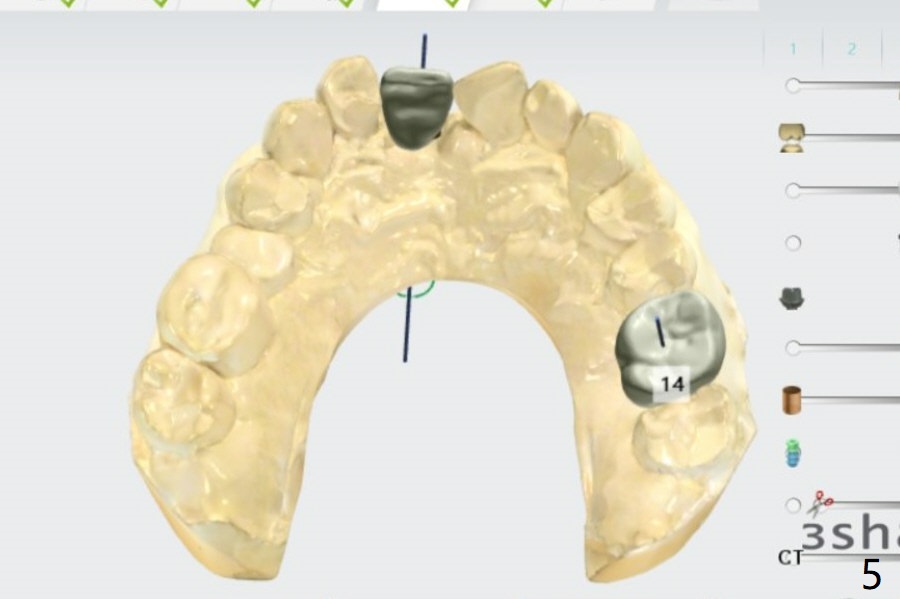

Narrow Implant with Angled Abutment

Return to Upper Incisor Molar Immediate Implant, Trajectory Protect Graft